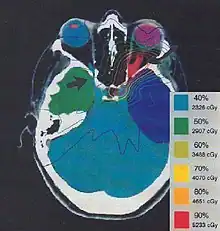

The more formal optimization process is typically referred to as forward planning and inverse planning.[12][13] Plans are often assessed with the aid of dose-volume histograms, allowing the clinician to evaluate the uniformity of the dose to the diseased tissue (tumor) and sparing of healthy structures.

Once the treatment planner has made an initial plan, the treatment planning system calculates the required monitor units to deliver a prescribed dose to a specific area, and the distribution of dose in the body this will create. The dose distribution in the patient is dependent on the anatomy and beam modifiers such as wedges, specialized collimation, field sizes, tumor depth, etc. The information from a prior CT scan of the patient allows more accurate modelling of the behaviour of the radiation as it travels through the patient's tissues. Different dose calculation models are available, including pencil beam, convolution-superposition and monte carlo simulation, with precision versus computation time being the relevant trade-off.